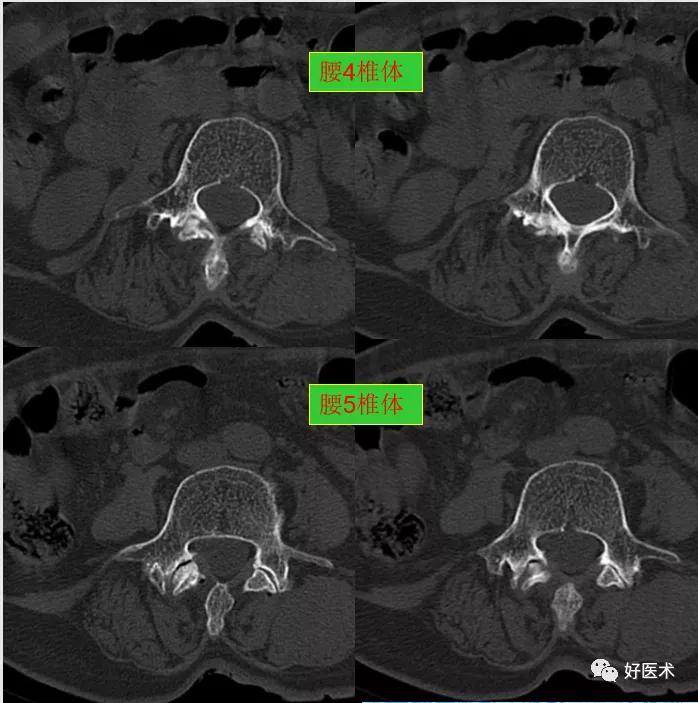

腰3-4间盘膨隆。

腰4-5间盘膨隆, 双侧椎小关节积气

腰5骶1间盘膨隆,双侧椎小关节积气